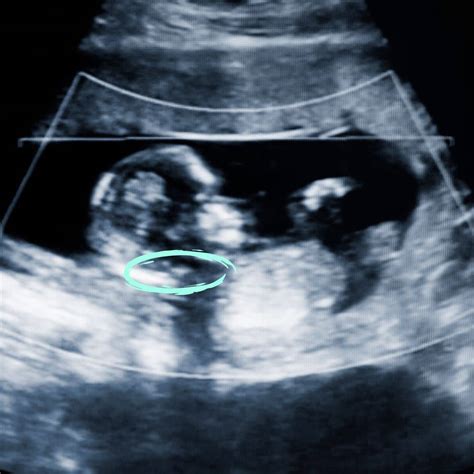

• Nuchal Translucency (NT) Measurement: This is a crucial part of the scan, where the sonographer measures the fluid-filled space at the back of the baby's neck. An increased measurement can indicate a higher risk of chromosomal abnormalities, such as Down syndrome.

• Heartbeat and Movement: The baby's heartbeat and movements will be checked to ensure everything is progressing normally.

• Anatomy Check: The sonographer will examine the baby's brain, spine, abdomen, and limbs to ensure proper development.